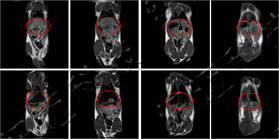

Images were acquired on a small-animal MRI system. Shown are T1-weighted axial and coronal images with the following parameters: FOV = 100 mm × 100 mm, TR = 400 ms, TE = 19 ms, slice thickness 3.5 mm, gap 1 mm, averages 16, k-space matrix 192 × 256. Post-contrast, the rat heart and liver appear brighter, then gradually darken with time as the agent is metabolised.

Rat MRI coronal images before and after contrast

Axial MRI showing in vivo metabolism of contrast agent in a rat